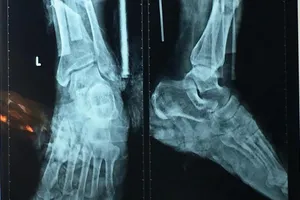

Nối 2 bàn chân gần đứt lìa do máy cắt cỏ

Nối bàn chân gần đứt lìa do máy cắt cỏ

Nối thành công bàn chân người đàn ông bị máy cắt cỏ cắt lìa

Đang cắt cỏ, người đàn ông bị đứt 2/3 bàn chân trái

Gãy lưỡi máy cắt cỏ làm đứt lìa 2 bàn chân

Sơ ý, cụ ông bị máy cắt cỏ chém suýt lìa cẳng chân